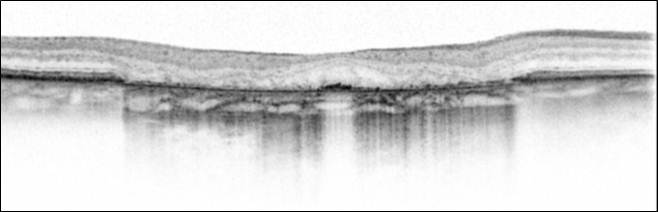

El artículo "Hyporeflective wedge-shaped band in geographic Atrophy secondary to age-related macular Degeneration: un underreported finding" ha sido publicado en el número de julio de la Revista científica Ophthalmology, revista oficial de la American Academy of Ophthalmology.

Los autores de este artículo, el Dr. Jordi Monés M.D., Ph.D., el Dr. Fábio Trindado y Marco Biarnés exponen un nuevo descubrimiento en las capas de la retina de personas con atrofia geográfica secundaria a degeneración macular asociada a la edad.

El Dr. Monés, director del Institut de la Màcula, manifestó que "este hallazgo puede ser de importancia en el entendimiento de los mecanismos de la enfermedad a nivel celular y podría contribuir a la investigación con nuevos fármacos experimentales".